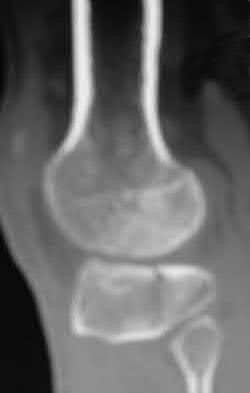

Figures A and B are radiographs and 3D reformatted CT images showing a displaced partial articular radial head fracture.